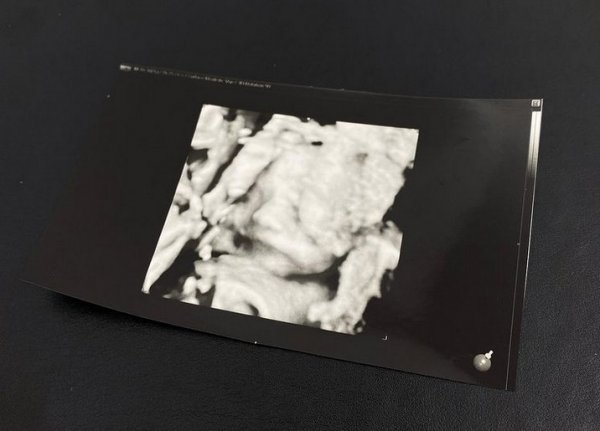

함께 공개한 사진은 권다미-김민준 부부 아기의 초음파 사진이다.